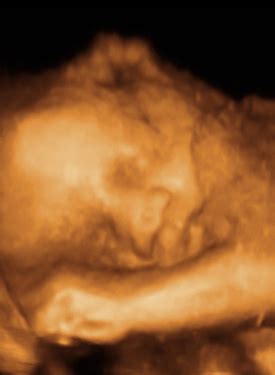

Web the stork's nest is located at 1740 s bell school rd in cherry valley, illinois 61016. Web the stork's nest is located at 1740 s bell school rd in cherry valley, illinois 61016. Web the stork's nest in cherry valley, il offers 2d, 3d & 4d ultrasound for pregnant women from early pregnancy through 40 weeks. Web the stork's nest, cherry valley, illinois.

Storks Nest Cherry Valley - Web the stork's nest, cherry valley, illinois. Web the stork's nest in cherry valley, il offers 2d, 3d & 4d ultrasound for pregnant women from early pregnancy through 40 weeks. Web the stork's nest is located at 1740 s bell school rd in cherry valley, illinois 61016. The stork's nest offers a variety of fetal imaging packages, from. Welcome to.